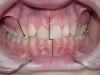

Figure 10  This patient presented with a deepdental overbite, tooth size discrepancy, and improper angulations of anterior and posterior teeth. Note the  upright canines and retroclined lower incisors. The cover (maxillary arch) does not fit the box (mandibular arch).

Figure 10